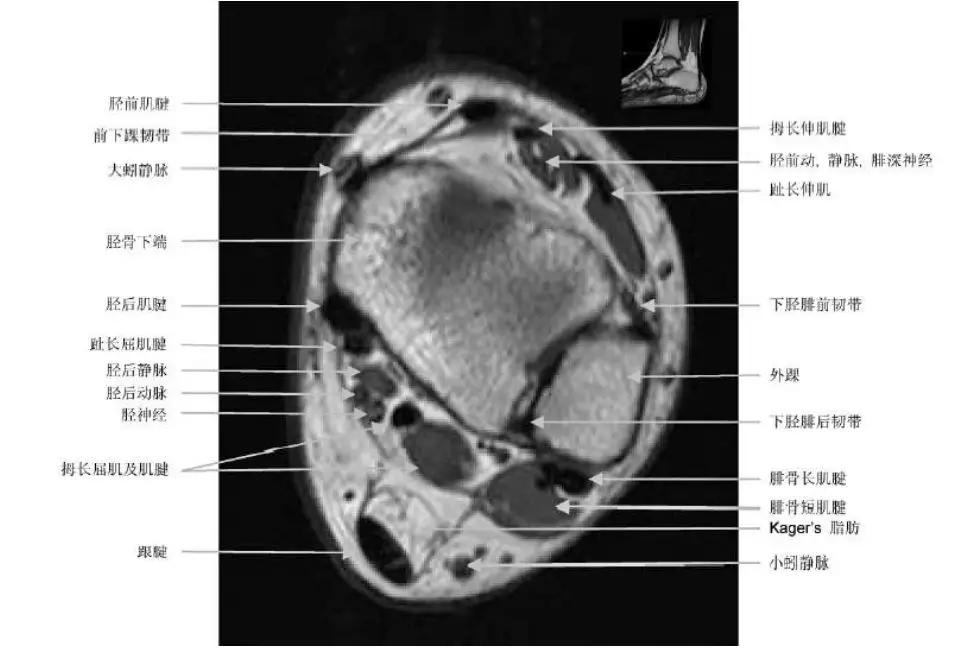

- 外侧:腓骨长肌和腓骨短肌;

- 内侧:胫骨后肌,拇长屈肌,趾长屈肌;

- 前侧:胫骨前肌,拇长伸肌,趾长伸肌;

- 后侧:跟腱。